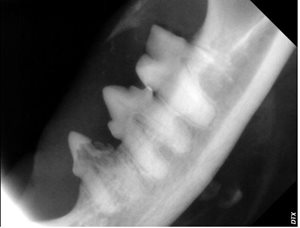

Another lovely feline friend, eight-year-old “Sir Ruby” had dentistry with us last month. During his annual health exam in May 2018, we observed that his teeth were moderately dirty, but by August 2018 there was significant suspicion of resorptive lesions noted by the veterinarian during a routine dental examination. The doctor noted the tell-tale red spot and significant gingivitis associated with his lower premolars. A dental procedure was recommended. During Sir Ruby’s dental surgery, gentle dental probing confirmed crown resorption and associated oral pain. X-rays of the affected teeth confirmed root resorption, as well. The teeth were extracted, Sir Ruby recovered quickly and is back to his normal happy self.

Right Lower Premolars